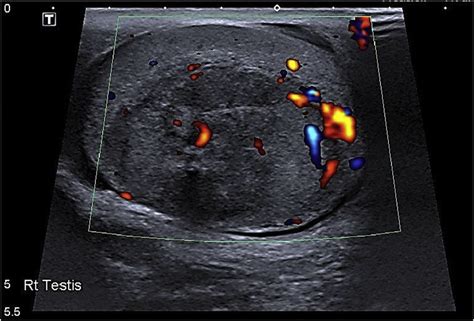

Heterogeneous hypoechoic lesion. A large heterogenous vascular mass, ...

Heterogeneous hypoechoic lesion.  A large heterogenous vascular mass, ...Heterogeneous hypoechoic lesion.  A large heterogenous vascular mass, ...